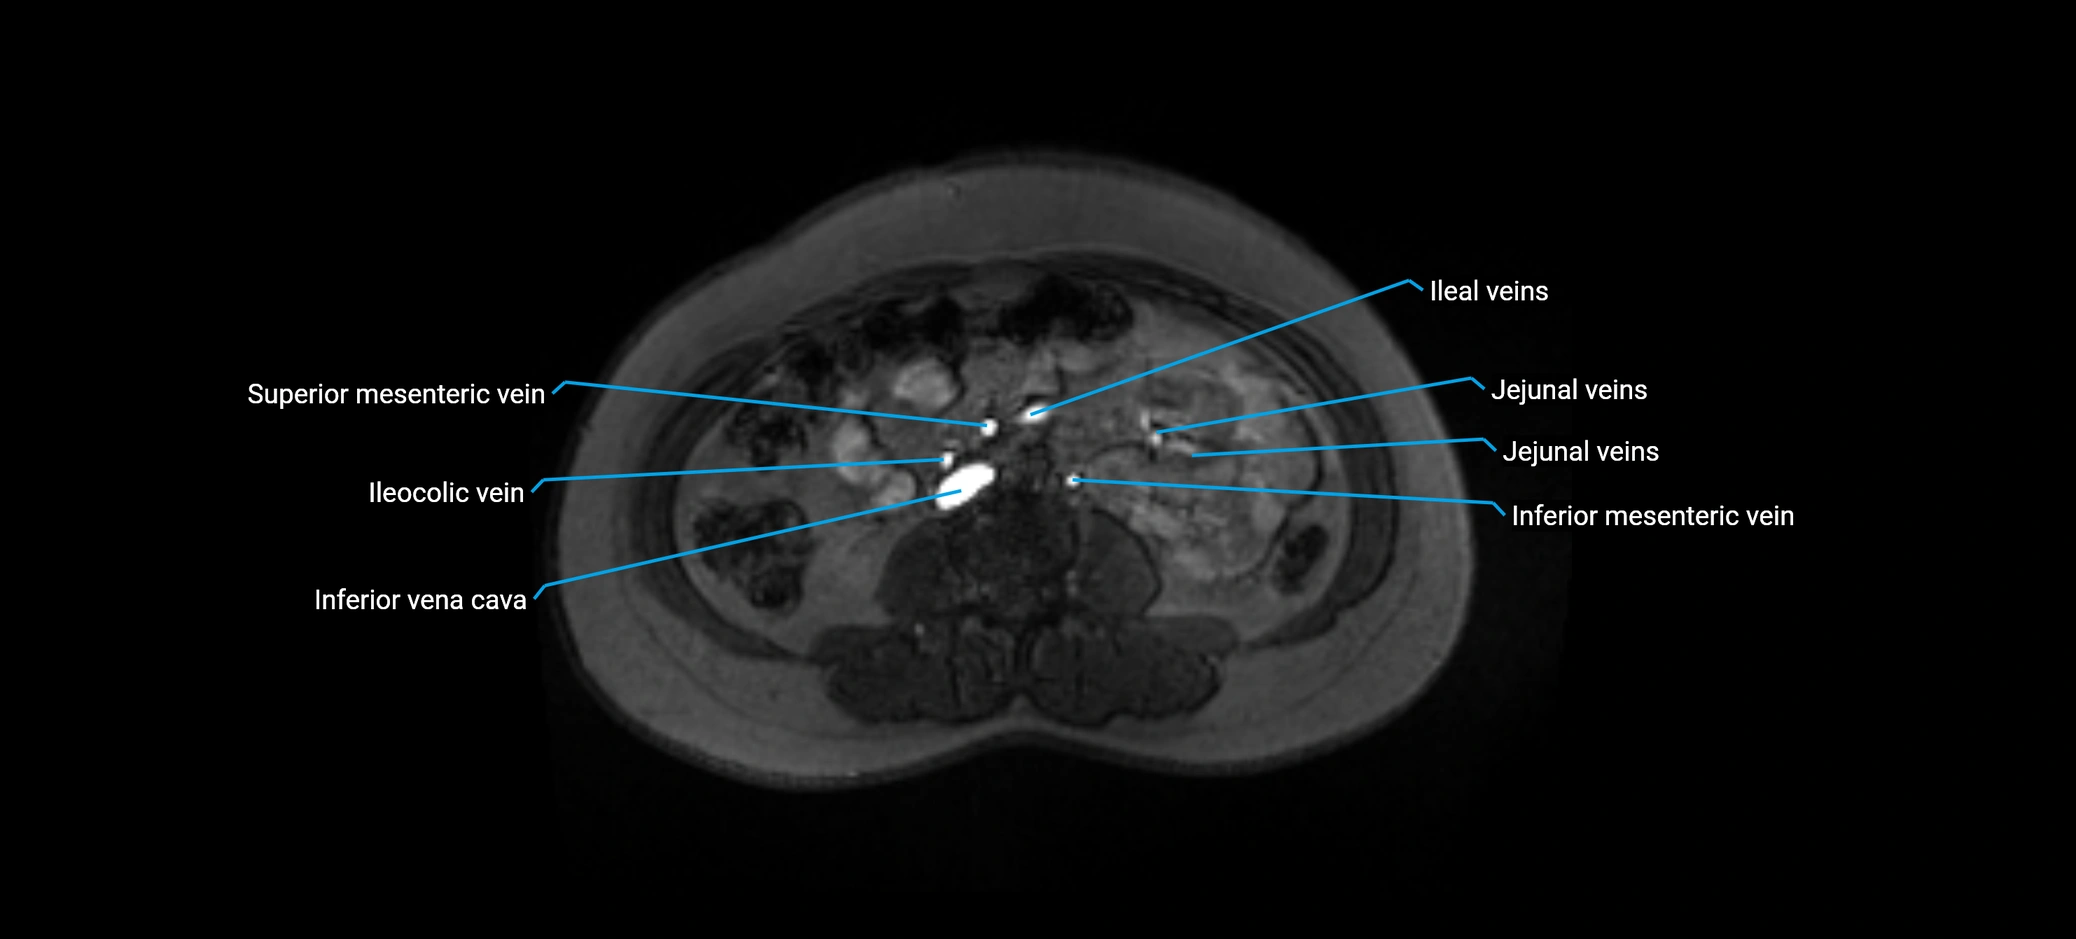

MRI image

image